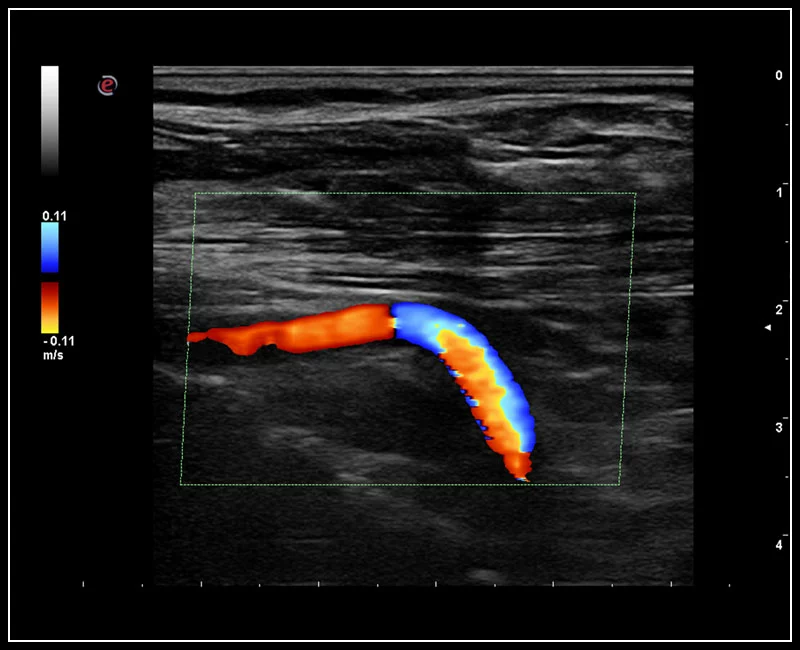

MyLab™C30 - Aorta

MyLab™C30 - Aorta